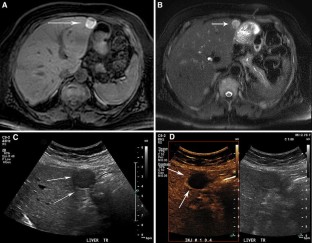

Fig. 4